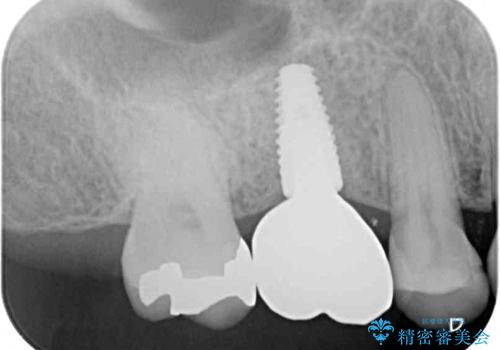

- 近医で奥歯の抜歯が必要であると指摘され、インプラント治療を希望して来院された患者様です。

診察の結果、大きな虫歯となっている歯は抜歯が望ましく、抜歯後にストローマンSLActiveを埋入することとしました。

機能性と清掃性、更には審美性も考慮し、土台となるアバットメントにはジルコニアカスタムアバットメントを採用しました。

ジルコニアカスタムアバットメントは、歯肉ラインに金属が見えにくいというだけでなく、クラウンを装着する土台の形が天然歯と近い形態となるため、清掃性が高く歯肉が腫れにくいというメリットがあります。